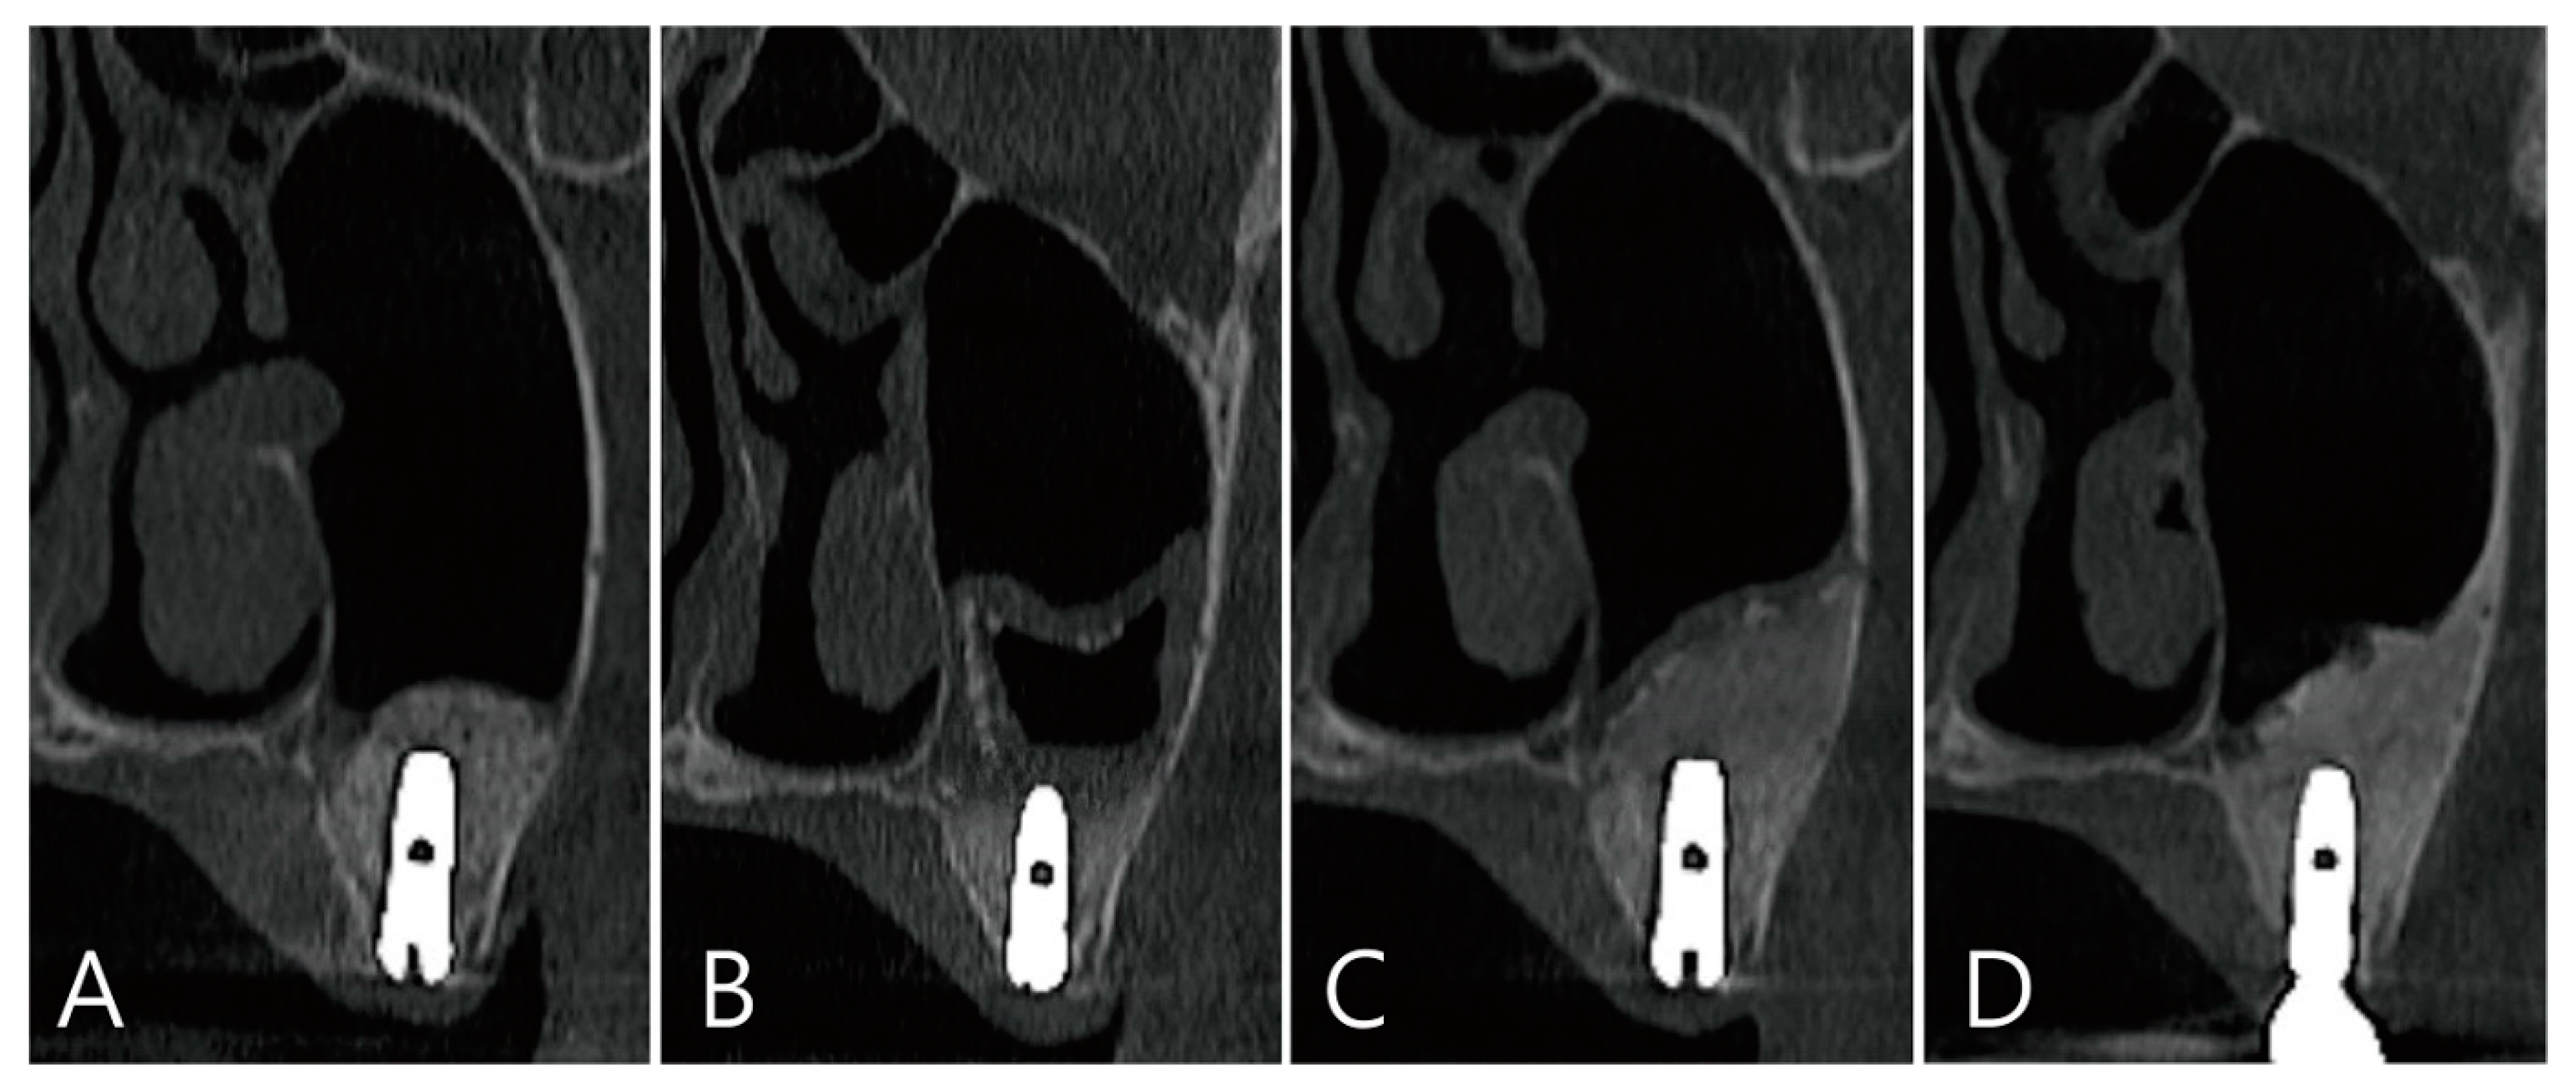

The coronal images of CBCT taken during the healing process after surgery were examined. There was no leakage of bone graft particles in the CBCT taken immediately after surgery (Figure 7A). One week after surgery, a large grafting void was developed over the apical third of the implant, and thickening of the sinus membrane was observed (Figure 7B). The shape of the grafting void after 6 months of surgery became clear and the size decreased. The sinus membrane thickening was also reduced. The void was filled with homogenous contents and showed a cystic appearance (Figure 7C). In the CBCT taken 6 months after the prosthesis was delivered, the bone graft substitute filled the grafting void well (Figure 7D).

Figure 7. Coronal images of the CBCT were taken at multiple points during the healing process after surgery: (A) an image taken immediately after surgery; (B) an image taken one week after surgery. A large grafting void occurred over the apical half of the implant, and thickening of the maxillary sinus mucosa was also observed; (C) in the image 6 months after surgery, the size of the grafting void was slightly reduced. The void presents with a cystic appearance resembling SCC. The apical bony support of the implant was lost. The grafting void was removed and additional bone grafting was performed; (D) in the CBCT image taken 6 months after the prosthesis was delivered, it can be confirmed that the previous grafting void was replaced with a bone graft substitute.